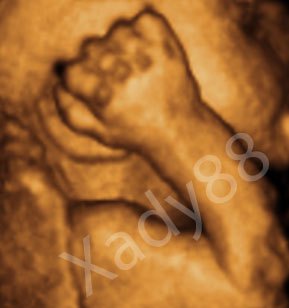

Her er mor og fars lille prinsesse

De to sidste er fra NF, hvor jeg var 12+